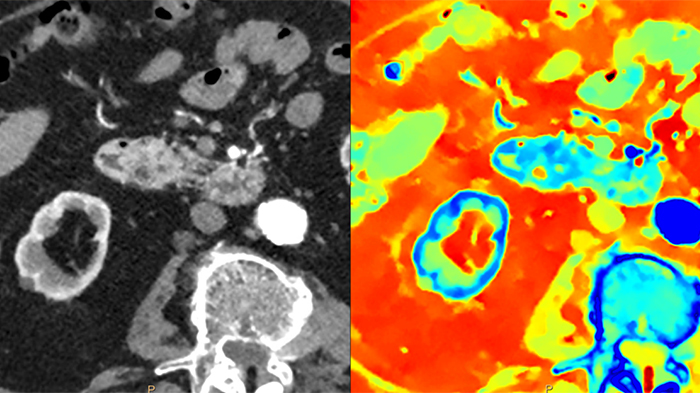

Im Gegensatz zur klassischen CT-Untersuchung beinhalten Spektraldetektor-CT-Daten immer auch spektrale Informationen, ohne spezielle Vorkehrungen oder zusätzliche Vorbereitungen. Das bedeutet, Sie können die Spektraldaten jeder Untersuchung auch retrospektiv mit unterschiedlichen Diagnosetools analysieren. Sie können beispielsweise die monoenergetischen Energielevel anpassen oder Z-effektive Bilder erhalten.

Der Spektraldetektor absorbiert und differenziert gleichzeitig die hohe und niedrige Energie eines einzigen polyenergetischen Röntgenstrahls. Spektralergebnisse werden in einem einzigen Scan ohne Einstellung separater Scan-Modi erfasst.

Ein CT-System mit Spektraldetektor absorbiert und differenziert gleichzeitig die hohe und niedrige Energie eines einzigen polyenergetischen Röntgenstrahls auf Detektorebene.